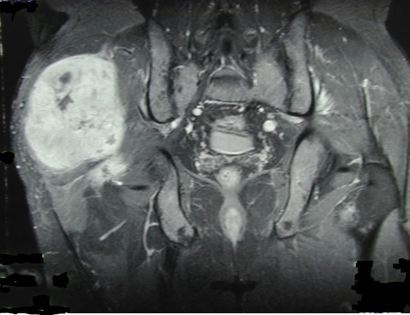

Pre-Op MRI of Tumor

On this MRI, the tumor can be identified as the brightened portion on the left hand side of the image. Although it is the left side of the image, it is actually on the right side of the human.